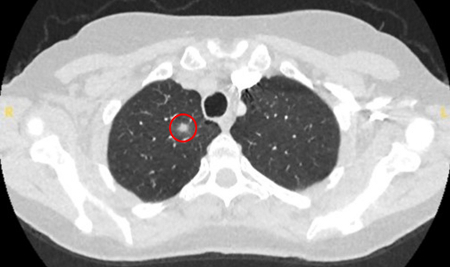

Tomografia computadorizada (TC) mostrando um pequeno nódulo no lobo superior esquerdo com margens lisas, posteriormente considerado uma metástase colorretal solitária na ressecção

Do acervo de Dr. George Tsaknis, MD, PhD, FRCP (Londres), MRQA, MAcadMEd, PGCert; usado com permissão